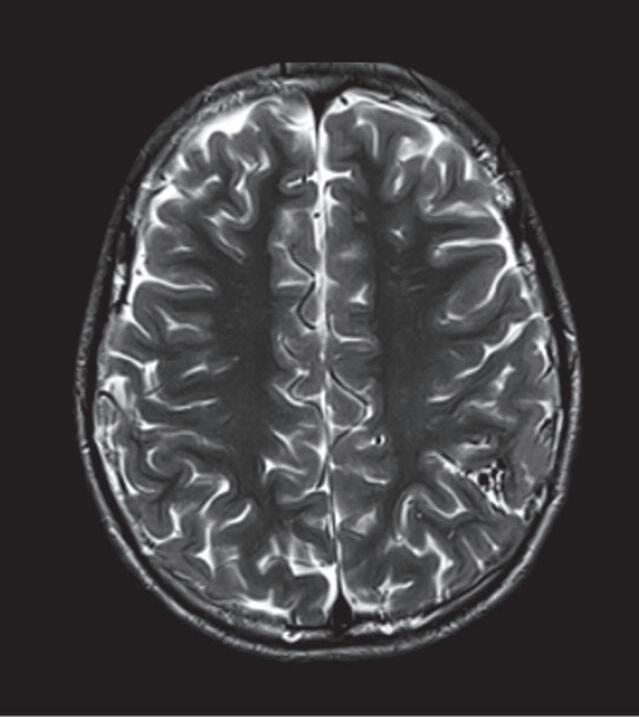

Fig. 1-14. RNM encéfalo, T2 axial (a) e coronal (b), demonstrando MAV grau 2 no lobo parietal esquerdo.

Arteriografia cerebral (c) AP e (d) em perfil, demonstrando a irrigação pelos ramos da artéria cerebral média (ACM) e anterior (ACA), com drenagem pela veia de Labbé, no seio transverso sigmoide.